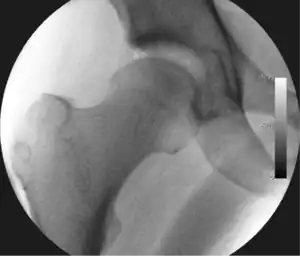

Figure 3. Fluoroscopic picture showing a mild amount of distraction of the hip before insertion of any instruments

The procedure is performed with the patient asleep (general anaesthetic) or under spinal anaesthesia. There are two widely used methods, one with the patient on their back (supine) and the other on their side (lateral decubitus). Which is used is down to the surgeon's preference. To gain access to the central compartment of the hip joint (between the ball and socket), traction is applied to the affected leg after placing the foot into a special boot. (See fig. 2) There is specifically designed equipment for this, although some surgeons use a 'traction table', initially designed to help in the operative fixation of broken thigh and lower leg bones. The amount of traction (or pull) needed is assessed with the help of fluoroscopy (low-dose portable x-ray). (See fig. 3) It is usually not possible to distract the ball from the socket with traction alone by more than a few millimetres. Once the surgeon is happy that they will be able to gain access to the hip joint (i.e. the ball will distract from the socket by a small amount), the patient is then painted with antiseptic and the surgical drapes applied.